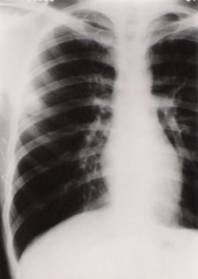

肺隱球菌病X片肺部隱球菌感染的初期,多數病人可無症狀。少數病人出現低熱、輕咳,咳黏液痰,偶有胸膜炎症狀。在愛滋病人中隱球菌感染經常是廣泛播散的。在免疫功能重度受損的病人中可以發生急性呼吸窘迫綜合徵(ARDS)。X線表現為多形性,輕者僅表現為雙肺下部紋理增加或孤立的結節狀陰影,偶有空洞形成。急性間質性炎症可表現為瀰漫性浸潤或粟粒樣病灶。需與肺結核、原發或轉移性肺癌鑑別。John.R.Perfect的經驗是隱球菌感染時,X線表現可以是在任何一個肺葉,任何類型的浸潤、結節或滲出都可以發生。近年來在同時有愛滋病毒(HIV)感染的病人中更常見的表現有酷似卡氏肺囊蟲感染的間質浸潤。由於肺部隱球菌感染可以與肺部其他疾病過程重複出現,所以X線更無典型特徵。

肺隱球菌病肺部隱球菌病可單獨存在,或與其他部位的隱球菌病同時發生。約1/3病例無任何症狀,常有胸部X線檢查中被發現,有時誤診為肺癌。多數患者可有輕度咳嗽、咳少量粘液痰或血痰、胸痛、低熱、乏力及體重減輕等。少數病例呈急性肺炎表現,偶有胸痛或肺實變和胸腔積液的體徵。當並發腦脊髓膜炎時,則症狀明顯而嚴重。常有中等度發熱,偶可高熱達40C,並出現腦膜腦炎的症狀和體徵。X線表現:病變以雙側中下肺部為多見,亦可為單側或局限於一肺葉。可呈孤立的大球形灶或數個結節狀病灶,周圍無明顯反應,類似腫瘤;或為瀰漫性粟粒狀陰影;或呈片狀浸潤陰影。約10%患者有空洞形成。

其他輔助檢查:X線表現可以是在任何一個肺葉,任何類型的浸潤、結節或滲出都可以發生。近年來在同時有HIV感染的病人中更常見的表現有酷似卡氏肺囊蟲感染的間質浸潤。由於肺部隱球菌感染可以與肺部其他疾病過程重複出現,所以X線更無典型特徵。